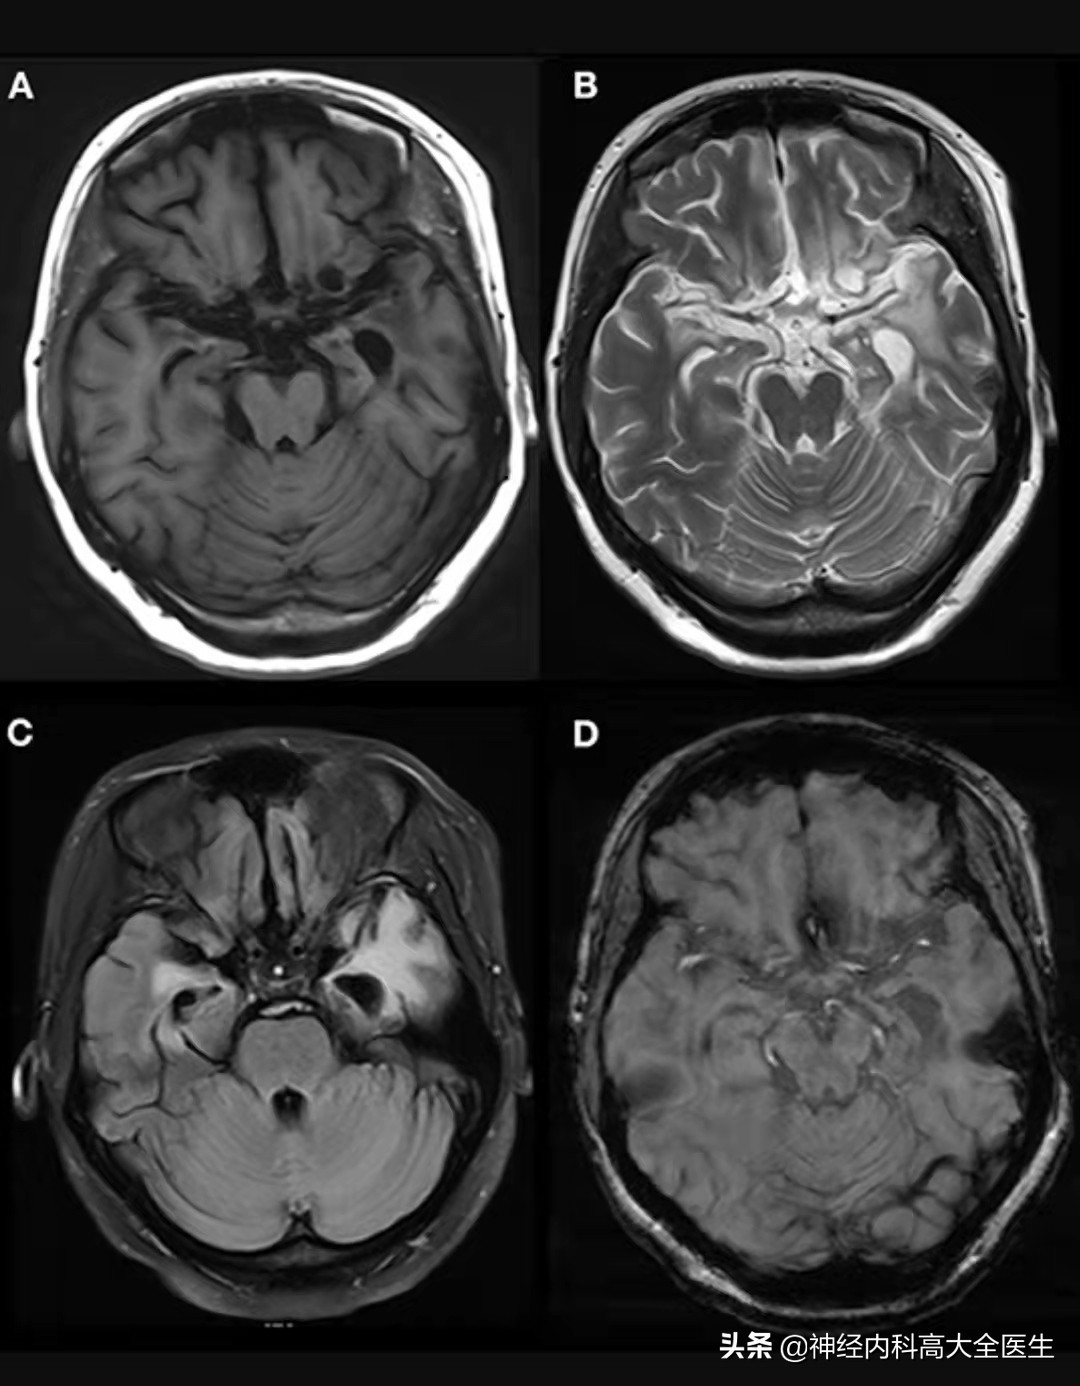

抗GABA-b受体脑炎影像学

抗GABAb受体脑炎急性期仅有 50%的患者头颅MRI异常,以颞叶和海马最易累及,多表现为T2/Flair高信号